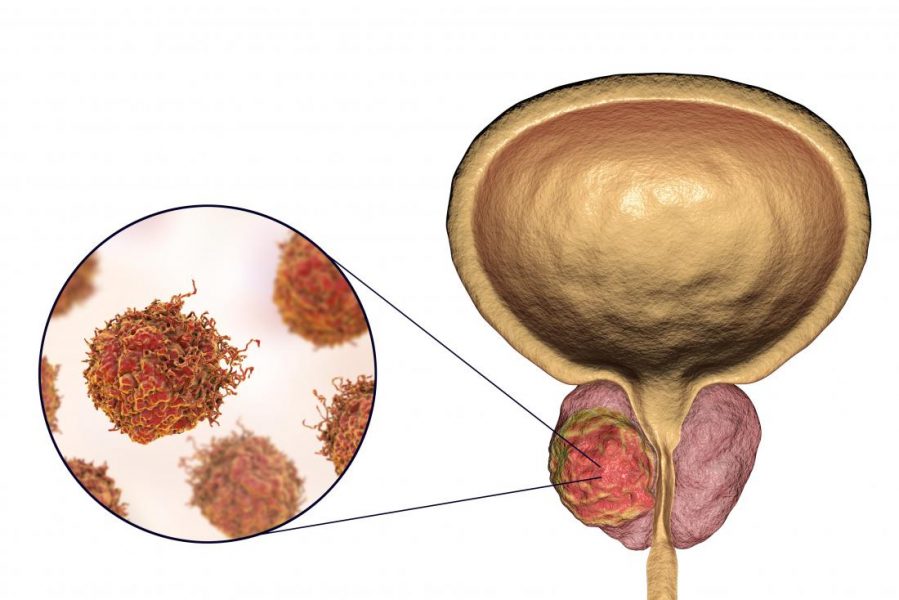

بیوپسی مغز استخوان یک آزمایش پزشکی است که در آن پزشک درخواست جمع آوری و بررسی نمونهای از مغز استخوان را میکند. این کار برای بررسی سالم بودن بافت و طبیعی بودن تولید سلولهای خونی انجام میشود. در این روش پزشک یک سوزن کوچک را در استخوان بزرگی فرو میکند و نمونهای از مغز استخوان […]